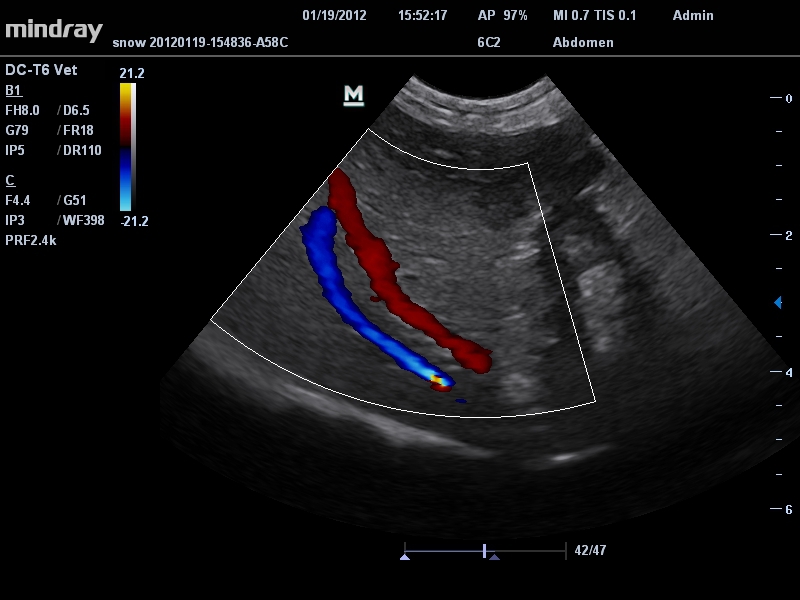

• Микроконвексный датчик Mindray 6C2

Ветеринария:

Да

• Режимы сканирования: B/M/CFM/PDI/Направленный PDI/PW, HPRF, Тканевая гармоника, М- и цветной М-режим.